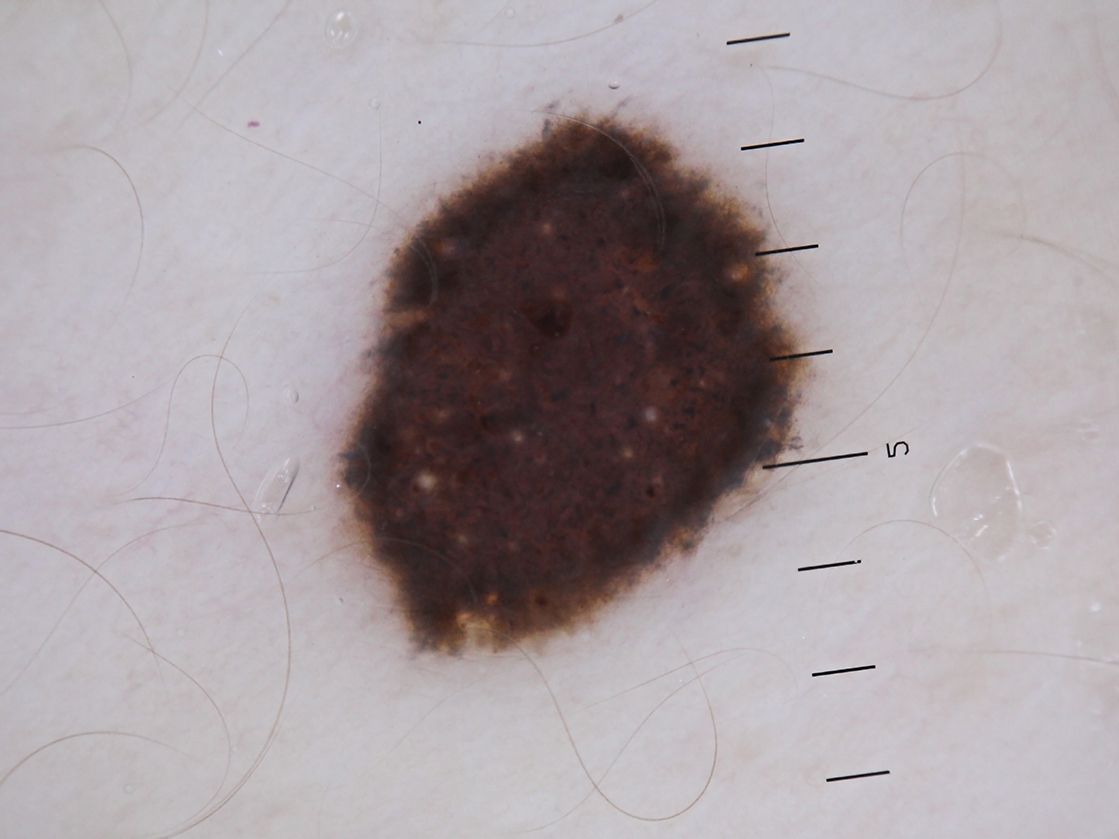

Hautkrebs und seine Vorstufen sind in der Regel mit dem bloßen Auge bzw. dem Dermatoskop (Auflichtmikroskop) sichtbar. Mit Hilfe von Selbstuntersuchungen (ABCDE-Regel) können Hautveränderungen frühzeitig entdeckt werden. Verändert sich ein über Jahre gleich gebliebener Leberfleck oder treten neue Leberflecke auf, empfiehlt es sich, diese einem Hautarzt zu zeigen.

ABCDE-Regel A - Asymmetrie: Verändert sich ein runder oder ovaler Leberfleck in eine asymmetrische Form oder entsteht ein neuer asymmetrischer Fleck, kann das ein Zeichen für ein Melanom sein. B - Begrenzung: Hat ein dunkler Hautfleck verwischte Konturen oder wächst ausgefranst in den gesunden Hautbereich, kann das ebenfalls ein Zeichen für ein Melanom sein. C - Color: Die Farbveränderung eines Leberflecks in mehrere Farben, von schwarz, braun bis rötlich-bläulich, ist ein ungünstiges Zeichen. D - Durchmesser: Hat eine Hautveränderung einen Durchmesser von mehr als 5 Millimetern oder zeigt eine schnelle Größenzunahme, kann das ein Zeichen für ein Melanom sein. E - Erhabenheit: Bildet sich in einem ursprünglich flachen Leberfleck ein Knoten oder eine raue, schuppende Oberfläche, kann das auf ein Melanom hindeuten. |